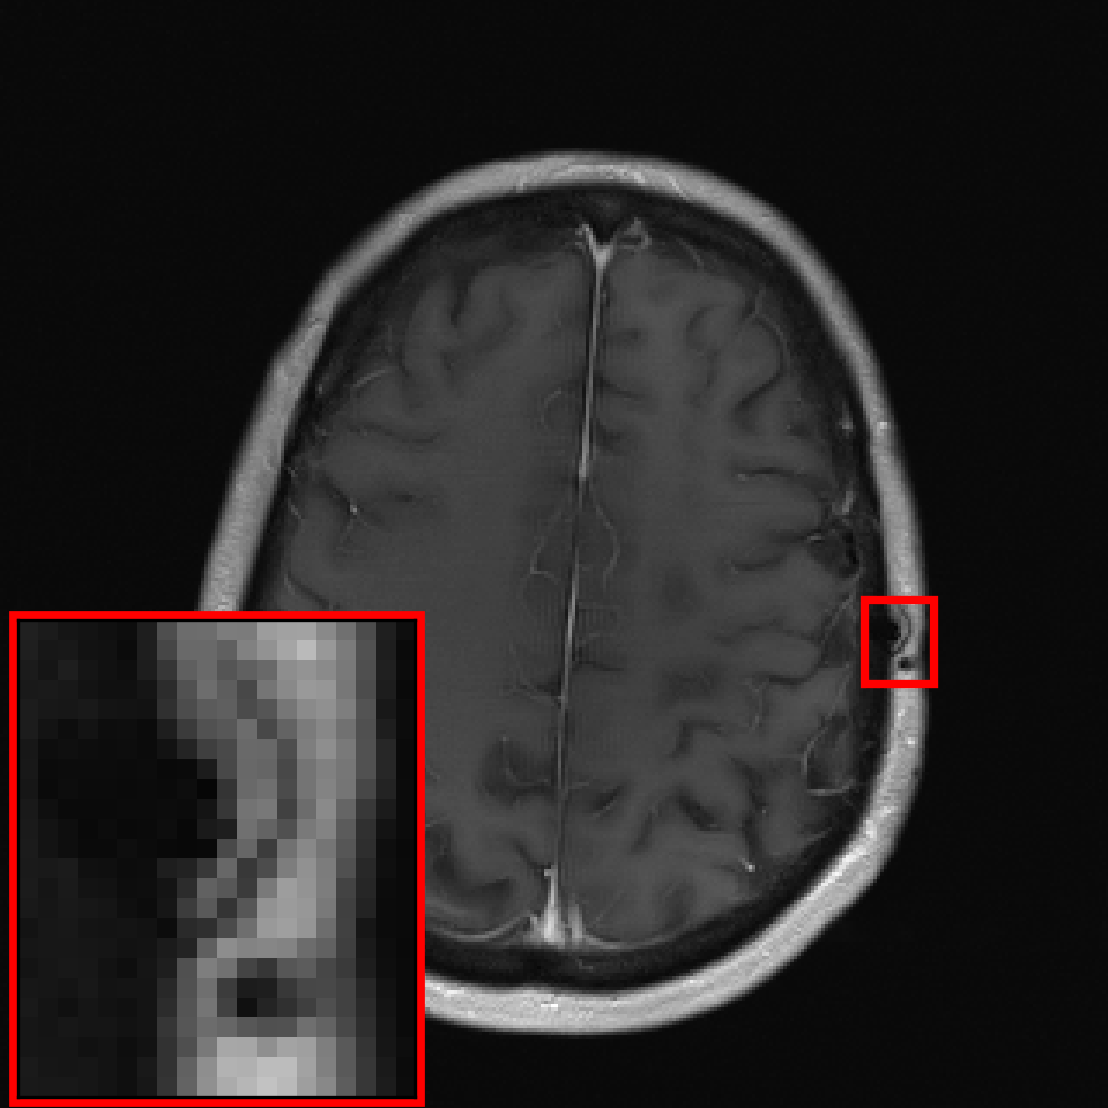

Many of our experiments are based on splits of the fastMRI dataset [Zbo+19], the most commonly used dataset for MRI reconstruction research. Figure 1 depicts samples from the fastMRI dataset and shows that MRI data varies significantly in appearance across different anatomies and image contrasts (FLAIR, T1, PD, etc). The image distribution also varies across vendors and magnetic field strengths of scanners, as the strength of the magnet impacts the signal-to-noise ratio (SNR), with stronger magnets leading to higher SNRs.

We see that the models trained on show essentially the same performance (SSIM) as models trained on regardless of pathology size. The results indicate that models trained on images without pathologies can reconstruct pathologies as accurately as models trained on images with pathologies. This is further illustrated in Figure 6 (and Figure 16), where we show reconstructions given by the VarNet of images with a pathology: the model recovers the pathology well even though no pathologies are in the training set. Figure 14 in the appendix provides a more nuanced evaluation of the SSIM values for VarNet.